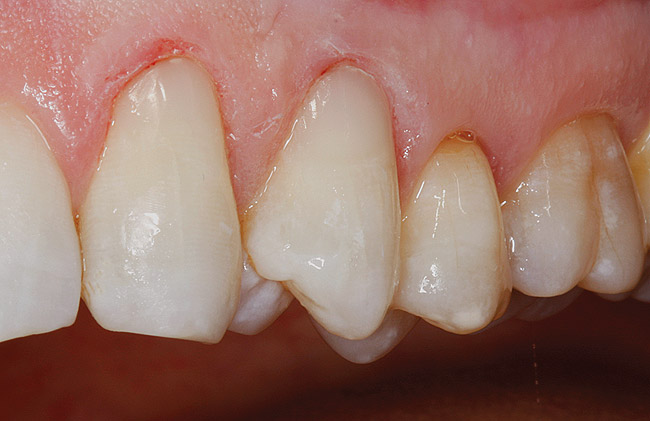

Figure  4  Possibly a combination of erosion and abrasion.

Figure 4

Characteristics of damage to tooth structures caused by acidity include wear on the occlusal surfaces of molars and a saucer shape on the cusps of molars (perimolysis).12 The erosion can vary from minor and subtle changes on the tooth surface, ie, loss of luster, a dull or matted look, to cupping on occlusal surfaces or incisal edges, which may extend to dentin. Usually, the erosive lesions demonstrate greater width than depth. When combined with abrasive forces or stresses, the tooth surface loss may occur at a faster rate (Figure 2, Figure 3, Figure 4 and Figure 5).